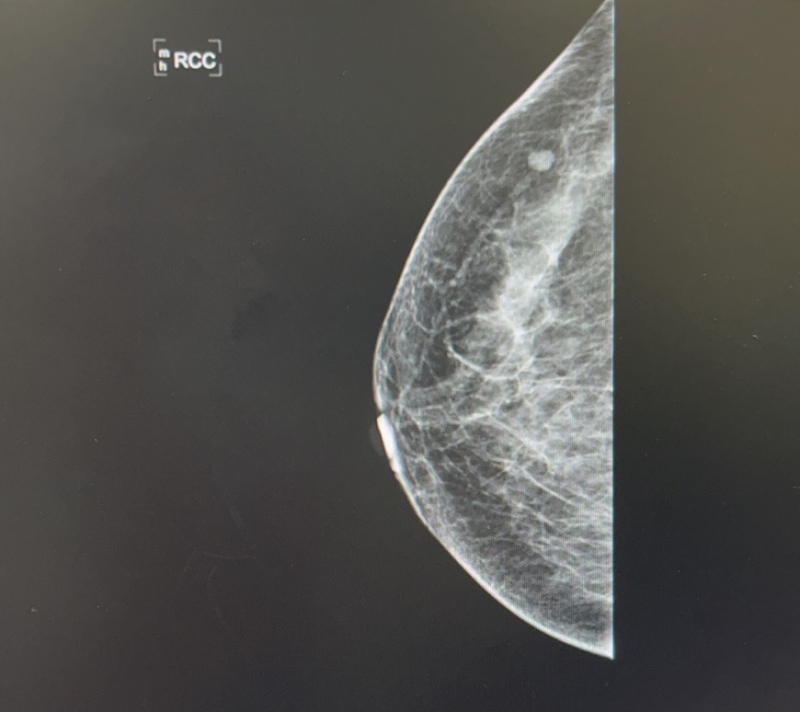

2023-05-14 日常动态 #x线下的艺术 1 评论 1 喜欢 分享 凹凸的世界 在这里带上了面具?,也是摘下了面具。 查看TA的全部内容 +关注 红楼go 去发现更多有趣内容 微信扫码打开红楼go小程序 体验更多「红楼go」新功能 评论 1 糖糖 2023-05-14 0 惊艳 我也来讲两句